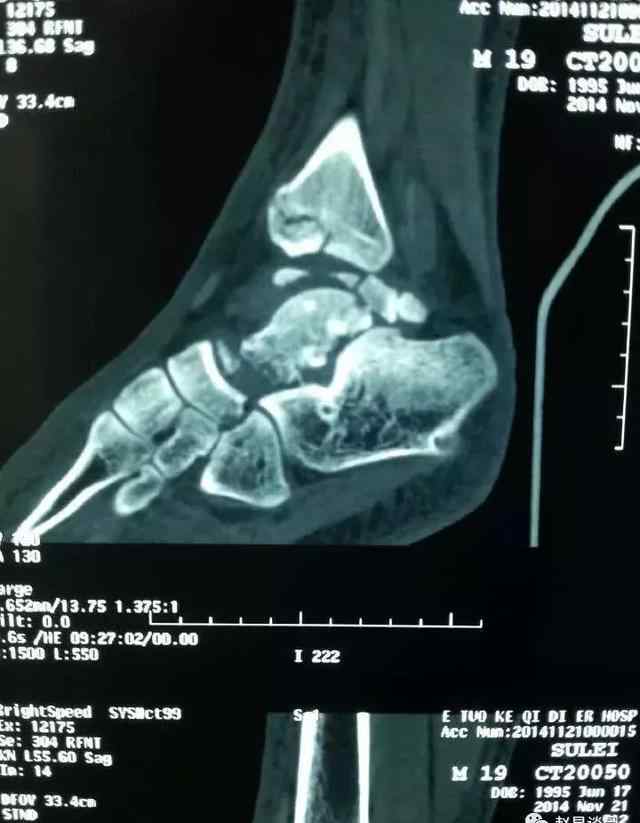

强直性脊柱炎是一种病程长、病因不明的自身免疫性疾病。以脊柱为主要病变部位,骶髂关节首先受累,然后逐渐向上进展,导致包括骶髂关节在内的轴骨及关节周围组织无菌性炎症,最后发展为完全的脊柱纤维化和骨性强直,也引起不同程度的眼、胃肠道、肺、心、肌、皮肤等疾病。

2.晚期严重影响关节功能

作为一种自身免疫性疾病,患者的关节经常受到自身免疫系统的攻击。如果没有针对性的治疗,而只是注意休息或给予腰肌劳损之类的一般治疗,疾病还是会发展的。当关节炎发展到最后,会导致关节完全坏死融合,功能丧失,患者甚至可能无法行走。

临床医生确实会看到这样的患者:被转到很多医院,但一直没有确诊,没有及时规范治疗,最终导致疾病进展,患病关节融合,发展为残疾,这是一种遗憾。

影像学检查对强直性脊柱炎的早期诊断非常重要,强直性脊柱炎患者血清HLA-B27检查比正常人更容易产生阳性结果。